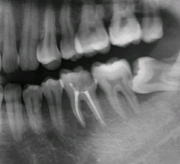

患者情況:郭先生,31歲,牙痛來診,主訴左下後牙反復疼痛,近日加重,開口受限。

醫生診斷:慢性根尖炎急性發作伴間隙感染

治療前